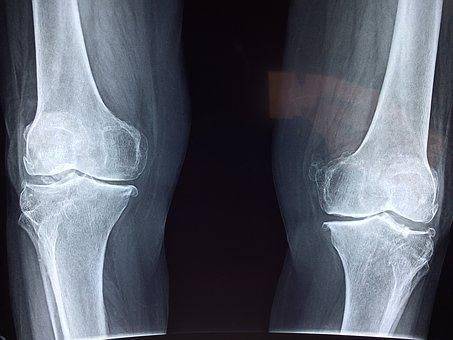

(二)应用医学

临床医学和预防医学不但要综合应用基础医学理论知识,而且还要不断为基础医学研究提出新的课题,促进医学的发展。它研究人体内外环境对健康的影响,及增进健康、防治疾病、延长寿命的方法和措施。主要学科包括临床医学、预防医学、康复医学、特种医学、放射医学、性医学、法医学、检验医学、护理医学等。